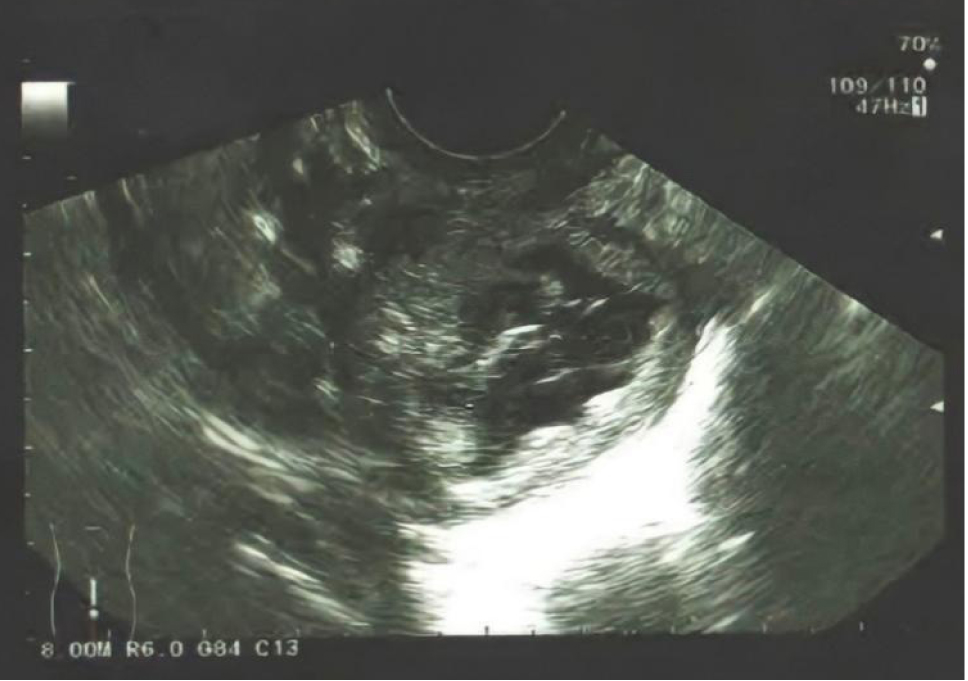

Пациентка К., 20 лет, обратилась к врачу-гинекологу с жалобами на боль во время полового акта и менструации. По результатам УЗИ (рис. 1): патологическое гетерогенное образование с ровными контурами и гипоэхогенным содержимым в позадиматочном пространстве, кровоток не регистрировался.

Рис. 1. Патологическое гетерогенное образование с ровными контурами и гипоэхогенным содержимым в позадиматочном пространстве, кровоток не регистрируется